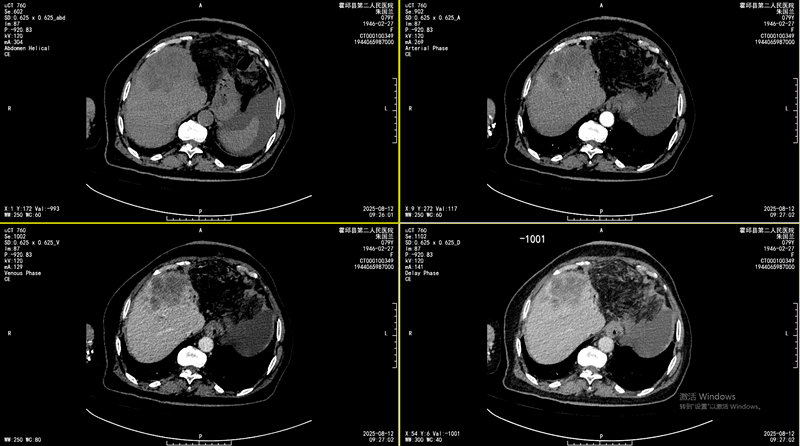

据了解, 患者朱女士(化名),79岁,因“腹痛,进食恶心、纳差”来我院就诊。既往无肝炎、肝硬化病史,CA199>1200U/ml,腹部增强CT检查提示肝脏占位,高度怀疑恶性肿瘤。为进一步明确诊断,我科团队为患者实施了CT引导下肝脏穿刺活检术,病理结果确诊为肝内胆管癌。这是一种恶性程度较高、治疗相对棘手的原发性肝癌类型。